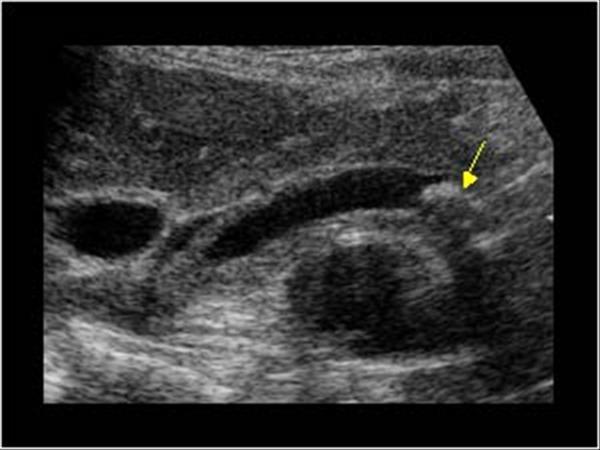

What is Polycystic liver disease?

This is an autosomal dominant genetic disease in which multiple small cysts cover the liver. 60% of patients with polycystic liver disease will have polycystic kidney disease.

What is the sonographic appearance of Polycystic liver disease?

Anechoic

Thin well-defined walls

Posterior

enhancement

Multiple

Varying in small size